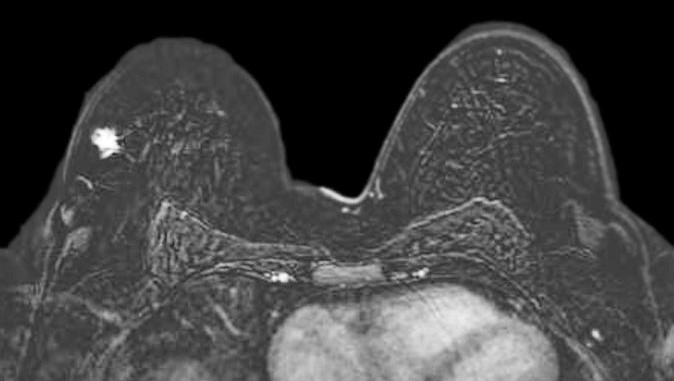

Breast MRI demonstrating breast cancer

Breast Imaging

PRI's breast imaging specialists bring decades of experience in the management of both benign and malignant breast disease. Our team is trained in the use of the most advanced breast imaging technology, including mammography, tomosynthesis, diagnostic mammography, breast MRI, and directed diagnostic ultrasound and whole breast screening ultrasound.

Collaboration is important to the success of comprehensive breast care. Our physicians cooperate with breast surgeons, medical oncologists, and radiation oncologists to help guide treatment decisions by integrating breast imaging information across all modalities. Our breast imaging specialists participate in weekly interdisciplinary breast cancer conferences.

Our breast imaging specialists have extensive experience in image-guided breast procedures, including stereotactic breast biopsy, ultrasound guided breast biopsy, and needle and radioactive seed pre-operative localization.